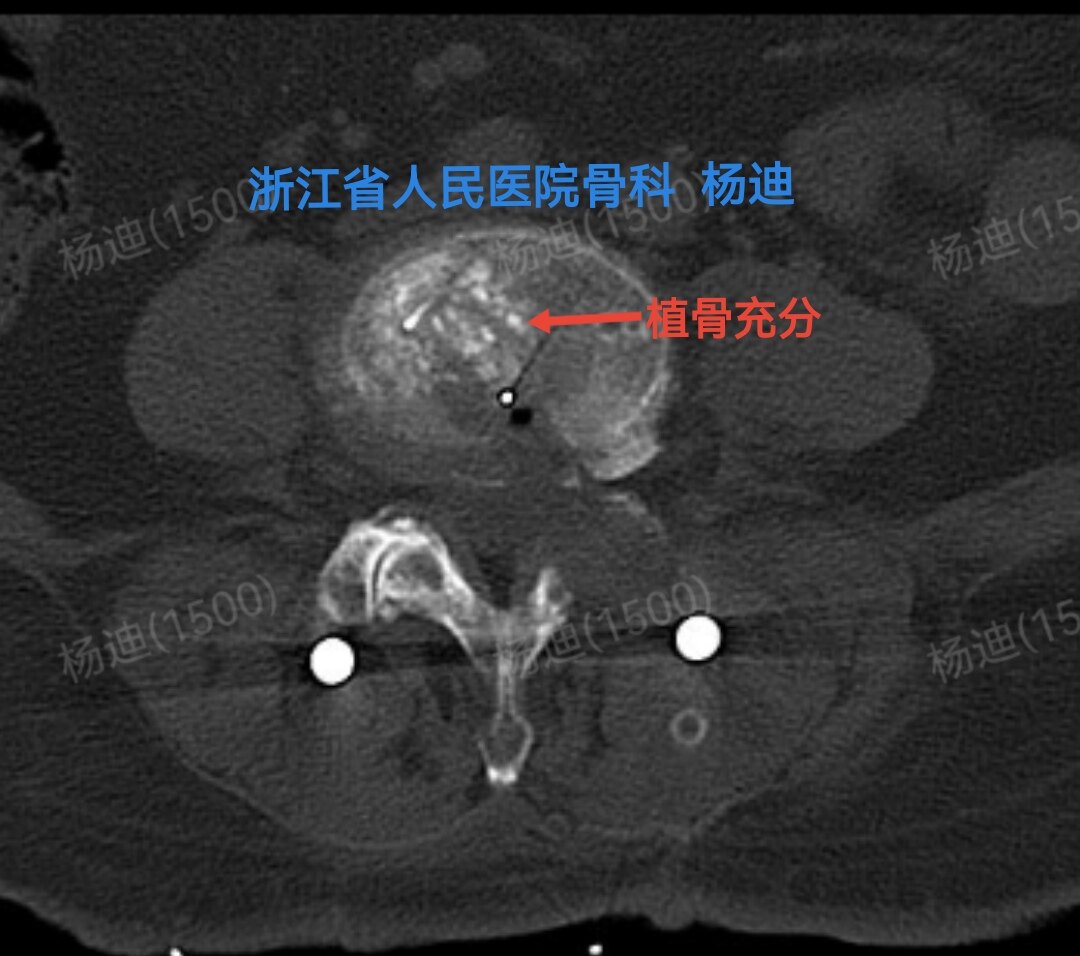

图为术后腰椎CT横断面,提示腰4/5间隙植骨充分(红色箭头)。

CT冠状位重建:椎间高度恢复(橙直线间距离),融合器位置良好植骨充分(红箭头),螺钉位置良好(黄圈)